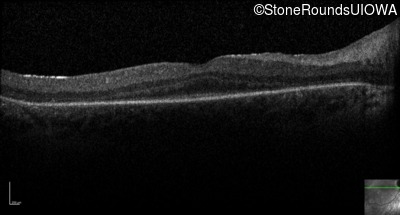

Optical Coherence Tomography - Right -

No Light Perception

Exemplar

Expanded OCT Stack

×